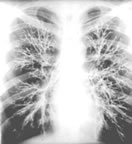

普通問質性肺炎

普通問質性肺炎,又叫間質性肺疾病、瀰漫性肺疾病等,作為病名,只有十多年的歷史,顧名思義它是肺間質的病變。間質性肺炎不是一個單一的疾病,而是一大類疾病的總稱,約有百餘種。

普通問質性肺炎,又叫間質性肺疾病、瀰漫性肺疾病等,作為病名,只有十多年的歷史,顧名思義它是間質的病變。間質性肺炎不是一個單一的疾病,而是一大類疾病的總稱,約有百餘種,已知一小部分病因已明,如塵肺、藥物性肺炎放射性肺炎等;但有相當一部分病因不明,如特發性肺纖維化、結節病等。間質性肺炎雖然稱為“肺炎”,但主要不是由細菌、病毒等微生物感染而成